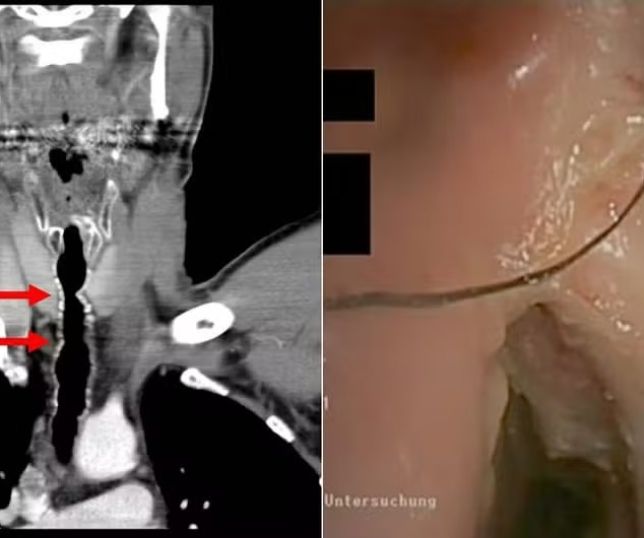

Com base nisso, os médicos inseriram uma pequena câmera pelas vias respiratórias do homem e encontraram fios de cabelo crescendo em uma área da garganta onde ele já havia passado por uma cirurgia.